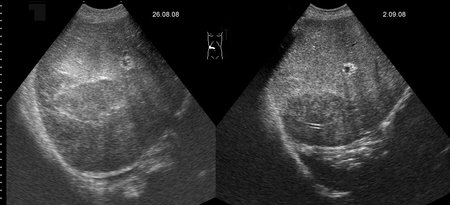

Маленький абсцесс печени до и на фоне 1 недели АБ-терапии

abscess-one_week_treatment.jpg

А какие ограничения для дренирования были в данном случае?

Плохая доступность. Был расположен очень высоко и был небольших размеров.

Решено было вести консервативно.